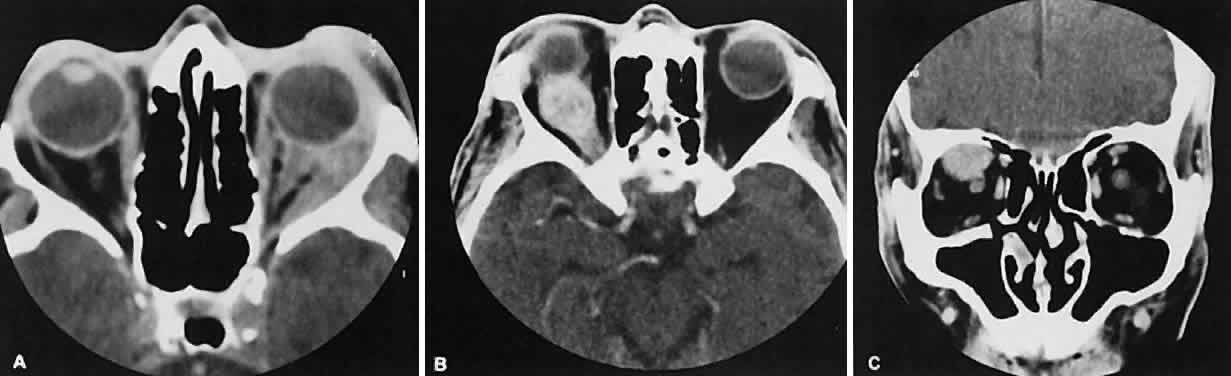

The CT evaluation of orbital myositis may show diffuse irregular enlargement of one or more EOMs; enlargement can be bilateral (Fig. 5). Incontradistinction to Graves' orbitopathy, involvement of the tendinous insertion and edema ofthe adjacent fat may be noted. Other conditions associated with EOM enlargement are listed in Table 2.31–33

Fig. 5. Axial views of orbital myositis. A. Note increased attenuation with enhancement of the thickened medial rectus and thickened scleral insertion. B. Thickening of the medial rectus muscle along the entire length of muscle is more evident.